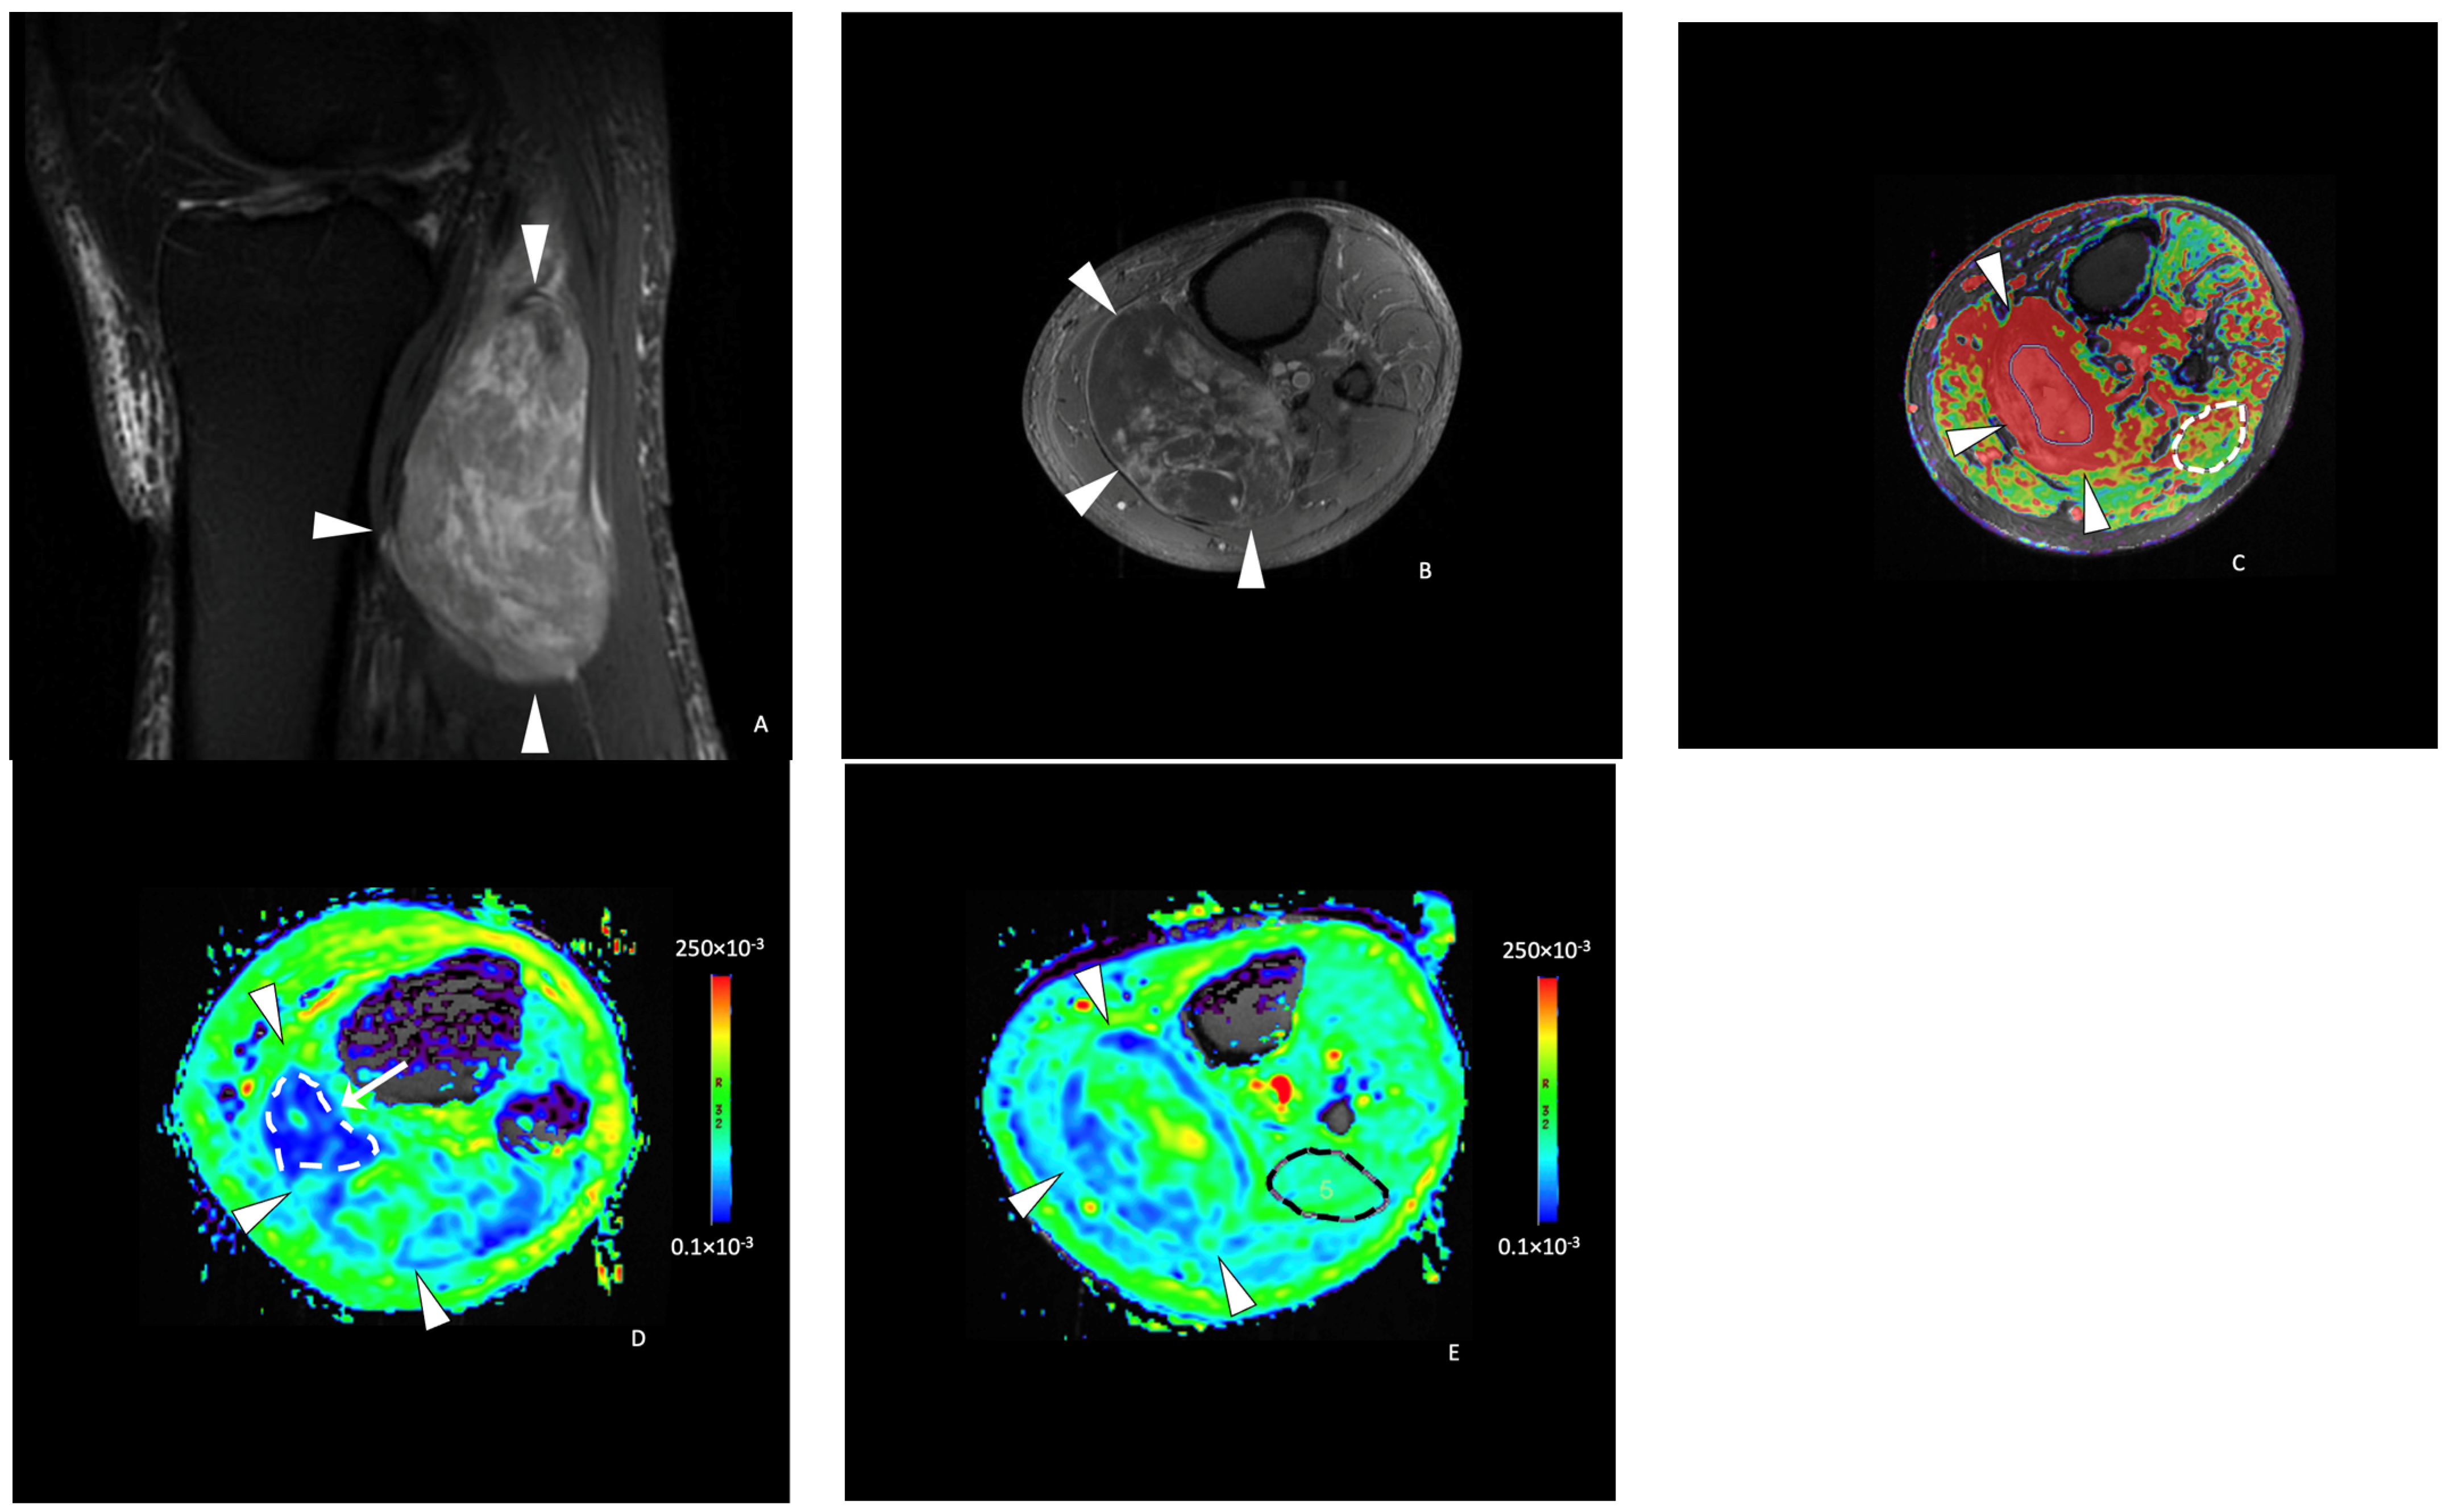

2.3. Image Post-Processing and Analysis

Functional MRI Analysis